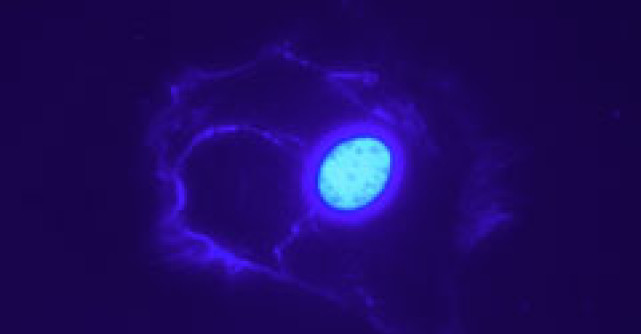

Programul de fertilizare in vitro - acum disponibil

fertilizare in vitro Pot participa la programul Ministerului Sanatatii unitati sanitare publice sau private care indeplinesc o serie de criterii, printre care acelea de a detine acreditare valabila pentru activitatea de utilizator de celule si tesuturi umane in scop terapeutic, acte doveditoare prin care personalul medico-sanitar isi exercita profesia in cadrul unitatii sanitare, documente care atesta pregatirea specialistilor in domeniul embriologiei umane si care fac dovada realizarii, incepand cu data de 1 ianuarie 2010, a minimum 50 de proceduri FIV/ET.